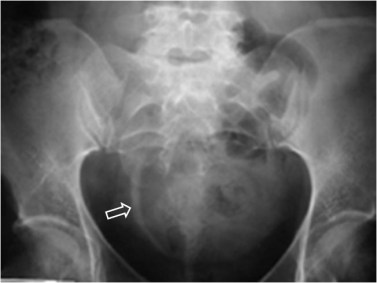

Signo visible en la radiografía simple de abdomen que permite diferenciar entre una vejiga muy distendida (globo vesical) y una masa pélvica de otro origen. La distensión de la vejiga se ve como una densidad homogénea redondeada u oval de borde superior definido, que ocupa la pelvis obliterando las zonas laterales de la pelvis y desplazando lateralmente el ciego y el sigma.

Las flechas negras marcan el borde superior vesical bien definido. Obsérvese el borramiento de planos grasos en la pelvis (flecha naranja), el desplazamiento lateral del ciego (flecha blanca) y superior del sigma (flecha roja).